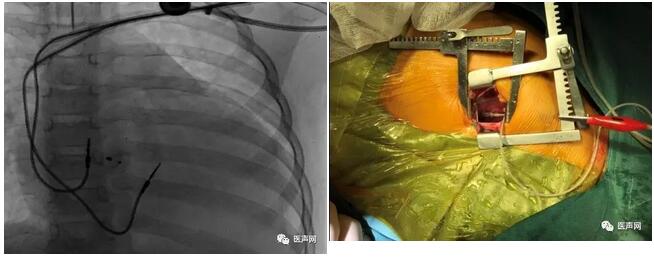

过程|说明:经左锁骨下静脉放置起搏右房、右室导线,左侧开胸小切口放置心外膜导线及囊袋制作

右室导线位置:右室间隔偏游离壁

左室导线位置:左室流出道偏游离壁

术中图片